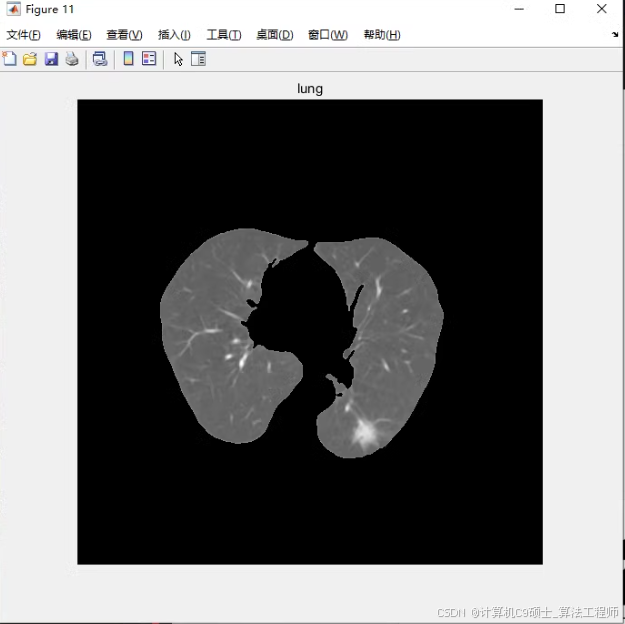

3、肺质分割。基于阈值分割,从原CT图像中分割出肺质;

肺质分割

肺质分割:segment_lung.m基于阈值分割从原CT图像中分割出肺质。